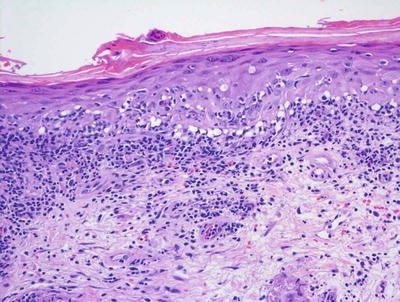

Lichen planus occurring in children has similar histologic features to the same disease in adults. The stratum corneum is hyperkeratotic without acanthosis. The epidermis is acanthotic with hypergranulosis (Fig. 4.2). The rete ridges demonstrate a saw-toothed alteration in appearance. The basal layer is disrupted and in some places obscured by a dense, band-like infiltrate of lymphocytes along the dermal epidermal junction (Fig. 4.3). Dying keratinocytes are present either focally or extensively, resulting in separation of the epidermis from the dermis. In some cases, this may present with clinically apparent bullae (bullous lichen planus) [2]. In older lesions, especially in patients with darker skin tones, post-inflammatory pigment incontinence is detected in the presence of papillary dermal melanophages (lichen planus pigmentosus in its most extensive form). The inflammatory infiltrate consists of lymphocytes and histiocytes. Eosinophils and plasma cells are not common. The infiltrate is restricted to the papillary dermis, and does not ordinarily extend into the reticular dermis [3–5].

Fig. 4.2

Lichen planus has orthokeratotic hyperkeratosis, hypergranulosis, acanthosis and a bandlike lymphocytic infiltrate in the papillary dermis